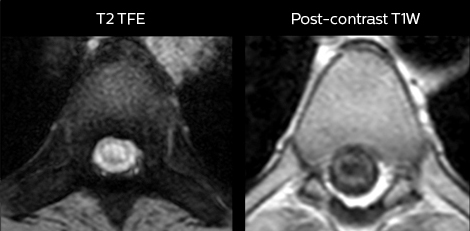

Pour minimiser la durée des acquisitions, des protocoles d’examen IRM rapides (ExamCards) ont été mis au point. Ils réduisent la durée d’acquisition totale à moins de 10 minutes pour certains examens. Des techniques comme le mDIXON (DIXON modifié) sont utilisées pour une acquisition solide des images d’IRM sans graisse dans l’environnement stressant des urgences.

“Nous utilisons beaucoup le mDIXON TSE dans notre imagerie du rachis en service d’urgences”, déclare le Dr Karis. “Ce qui est particulièrement appréciable, c’est sa fiabilité par rapport au type de susceptibilité des problèmes pouvant survenir avec des images spectrales classiques saturées en graisse ; ces problèmes sont essentiellement éliminés grâce à la technique mDIXON. C’est vraiment un avantage de disposer de l’imagerie sans graisse nécessaire à la technique mDIXON dans notre service d’urgences.”

“Pour les examens de routine sans contraste du rachis cervical et thoracique, par exemple, nous réalisons une séquence mDIXON T2 TSE qui produit deux sorties : les images pondérées en T2 avec graisse et eau, et les images sagittales pondérées en T2 avec eau uniquement. Ensuite, nous réalisons également un examen échographique du gradient axial.”